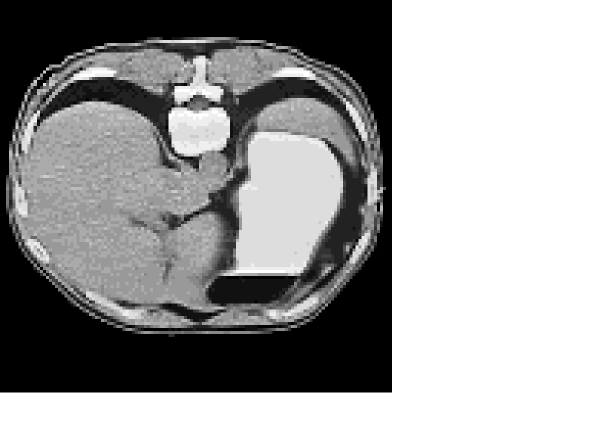

To simulate the internal data , we use an abdominal human CT image rescaled to a realistic range of tissue conductivity, with values varying from 1 to 1.8 S/m The scaled conductivity distribution, on a uniform grid , is shown in Figure 1.